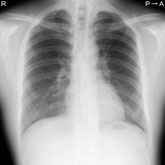

○ 肺がん

肺がん検診の受け方

市町村から送られてくる「受診券」と「自己負担金」をお持ちになって来院ください。簡単な問診と、胸部X線写真にて行います。問診により喫煙歴の基準を超える方には喀痰検査(かくたんけんさ)も実施いたします。

※ 喀痰検査は痰を採取いただく検査で、採取容器に付属の封筒にて郵送していただくことになります。